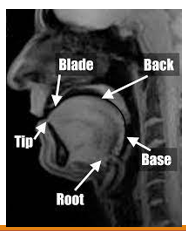

Parts of the tongue

Blade (body), back, tip (apex), base, root